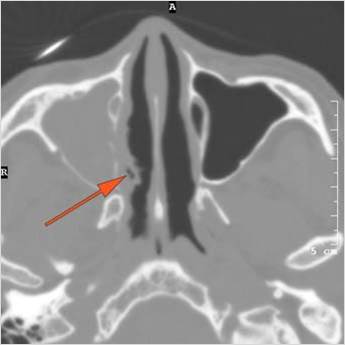

There is infiltration of the fat surrounding the nasolacrimal sac. [Yes/No]

There is infiltration of soft tissues or bone erosion along the nasolacrimal fossa or canal. [Yes/No]